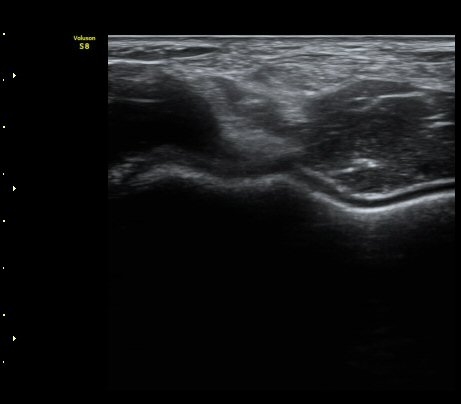

ÆÈ²ÞÄ¡ µÚÂÊ °üÀý¸éÀ¸·ÎºÎÅÍ 2.5cm ¾Æ·¡¿¡¼­ ¿ä°ñ°ü°ú ô°ñ °æ°èºÎ¸¦ Ⱦ´Ü¸éÀ¸·Î

°Ë»çÇÏ´Ï ¿ä°ñµÎ¿¡ ºÎÂøµÈ À̵ιڱ٠ÈûÁÙÀÌ °üÂûµÈ´Ù(±×¸² 9). Á¾´Ü¸é°Ë»ç¿¡¼­µµ

À̵ιڱ٠ÈûÁÙ°ú ¿ä°ñµÎ°¡ ¶Ñ·ÈÈ÷ °üÂûµÈ´Ù(±×¸² 10).